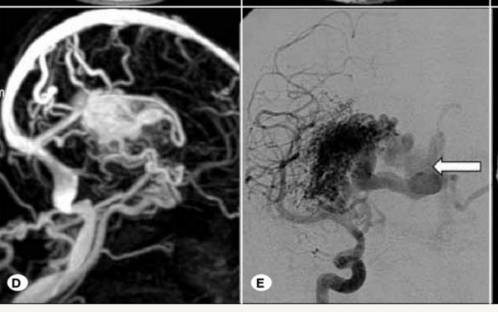

Imagen

A

TAC: Se vería sangre en caso de rotura. HSA o IP

AngioTC

RM: Maraña de vasos, vacios de señal

RM

GS

angiografía